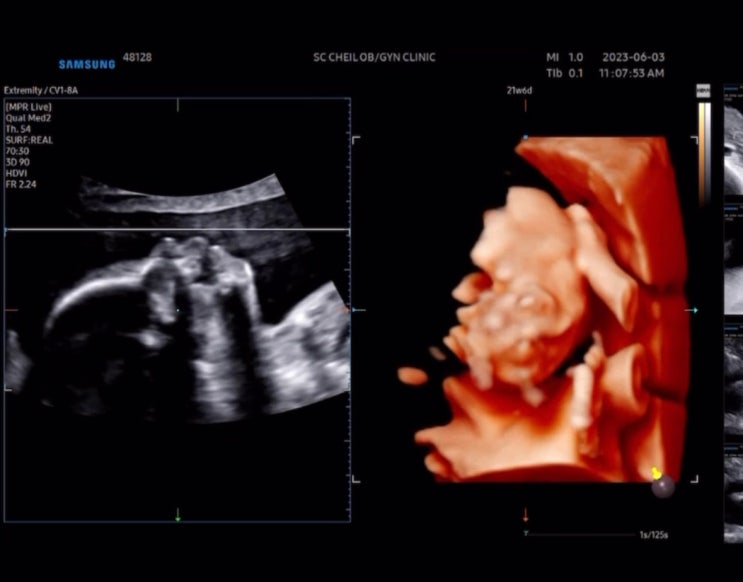

나트랑 태교여행 이후 처음으로 민준이랑 함께한 해외여행! 남편이랑 나는 참 해외여행 좋아해서 민준이 없...